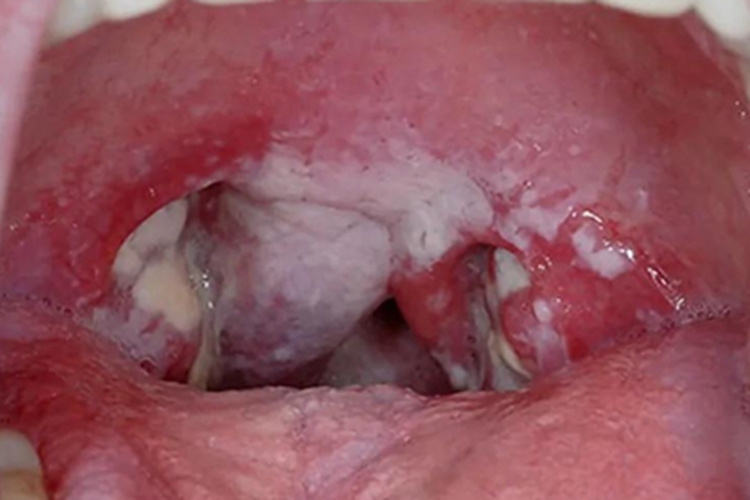

鹅口疮患者的咽喉部位表现为白斑,可以相互融合成大片,伴低热、拒食、吞咽困难。是由于口腔黏膜感染白色念珠菌引起。

鹅口疮主要表现为口腔黏膜表面覆盖白色乳凝块样小点或小片状物,可逐渐融合成大片,不易擦去,周围无炎症反应,强行剥离后局部黏膜潮红、粗糙,可有溢血,不痛,不流涎,一般不影响吃奶,无全身症状。重症患儿全部口腔均被白色斑膜覆盖,甚至可蔓延到咽喉处,伴低热、拒食、吞咽困难。